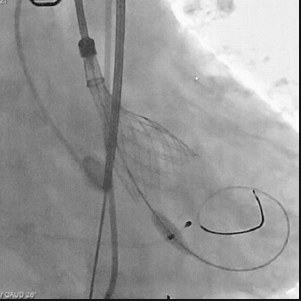

从三叶瓣重度钙化到二叶瓣畸形的根部解剖,从单纯主动脉瓣反流到入路极端迂曲挑战的案例。TaurusOne凭借其优异的柔顺性,支撑力强及内外层双侧裙边的特点,都能从容应对复杂的临床患者解剖结构。从患者的临床选择到术后的长久获益,从手术入路的种类到术中操作的注意事项,从围术期卒中的循证医学到术后的抗凝抗栓用药规范,在线专家共同交流彼此中心的围术期TAVR经验和分享现阶段经导管主动脉瓣置换的诊疗策略。针对当前TAVR领域多个热点学术问题进行了热烈的讨论,现场可谓精彩纷呈、高潮迭起。专家们纷纷借此契机相互交流探讨,分享各自的单中心经验,力求进一步提升TAVR手术的安全性和有效性,为主动脉瓣相关疾病的患者带来长远综合获益。